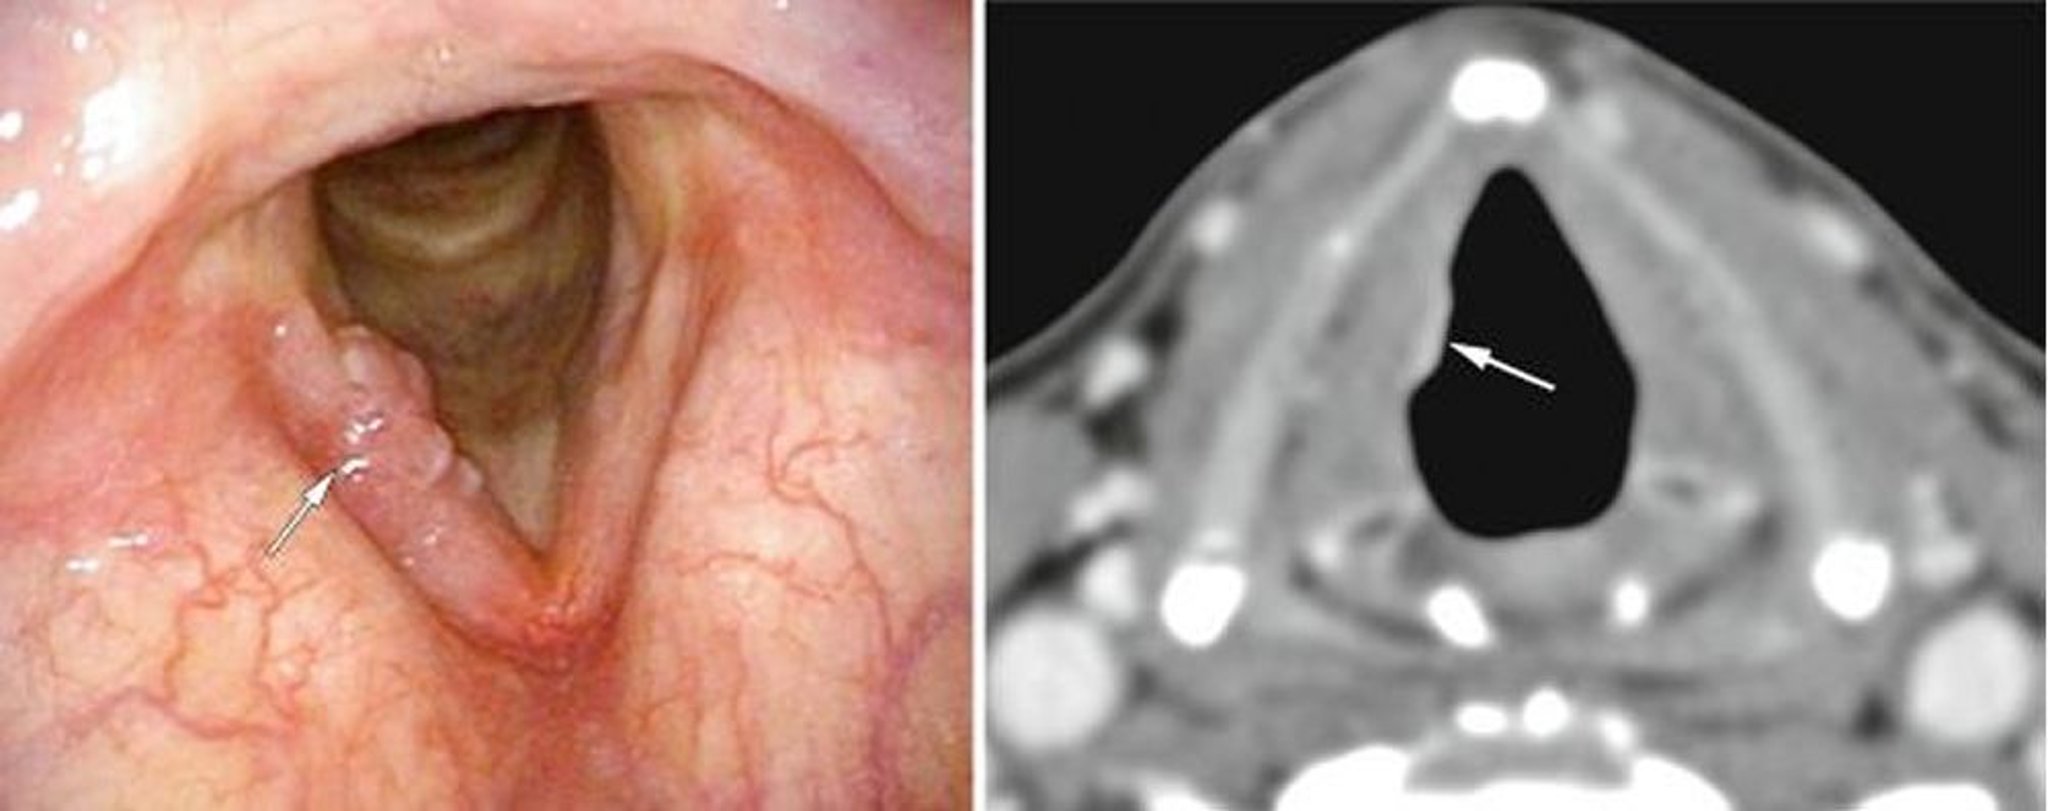

Cáncer de laringe temprano

Este paciente tenía un cáncer inicial de la porción glótica de la laringe, aquí visible en una cuerda vocal en la endoscopia (imagen de la izquierda, flecha blanca) como excrecencias, y en la TC (imagen de la derecha, flecha blanca) como una densidad anormal del tejido blando.